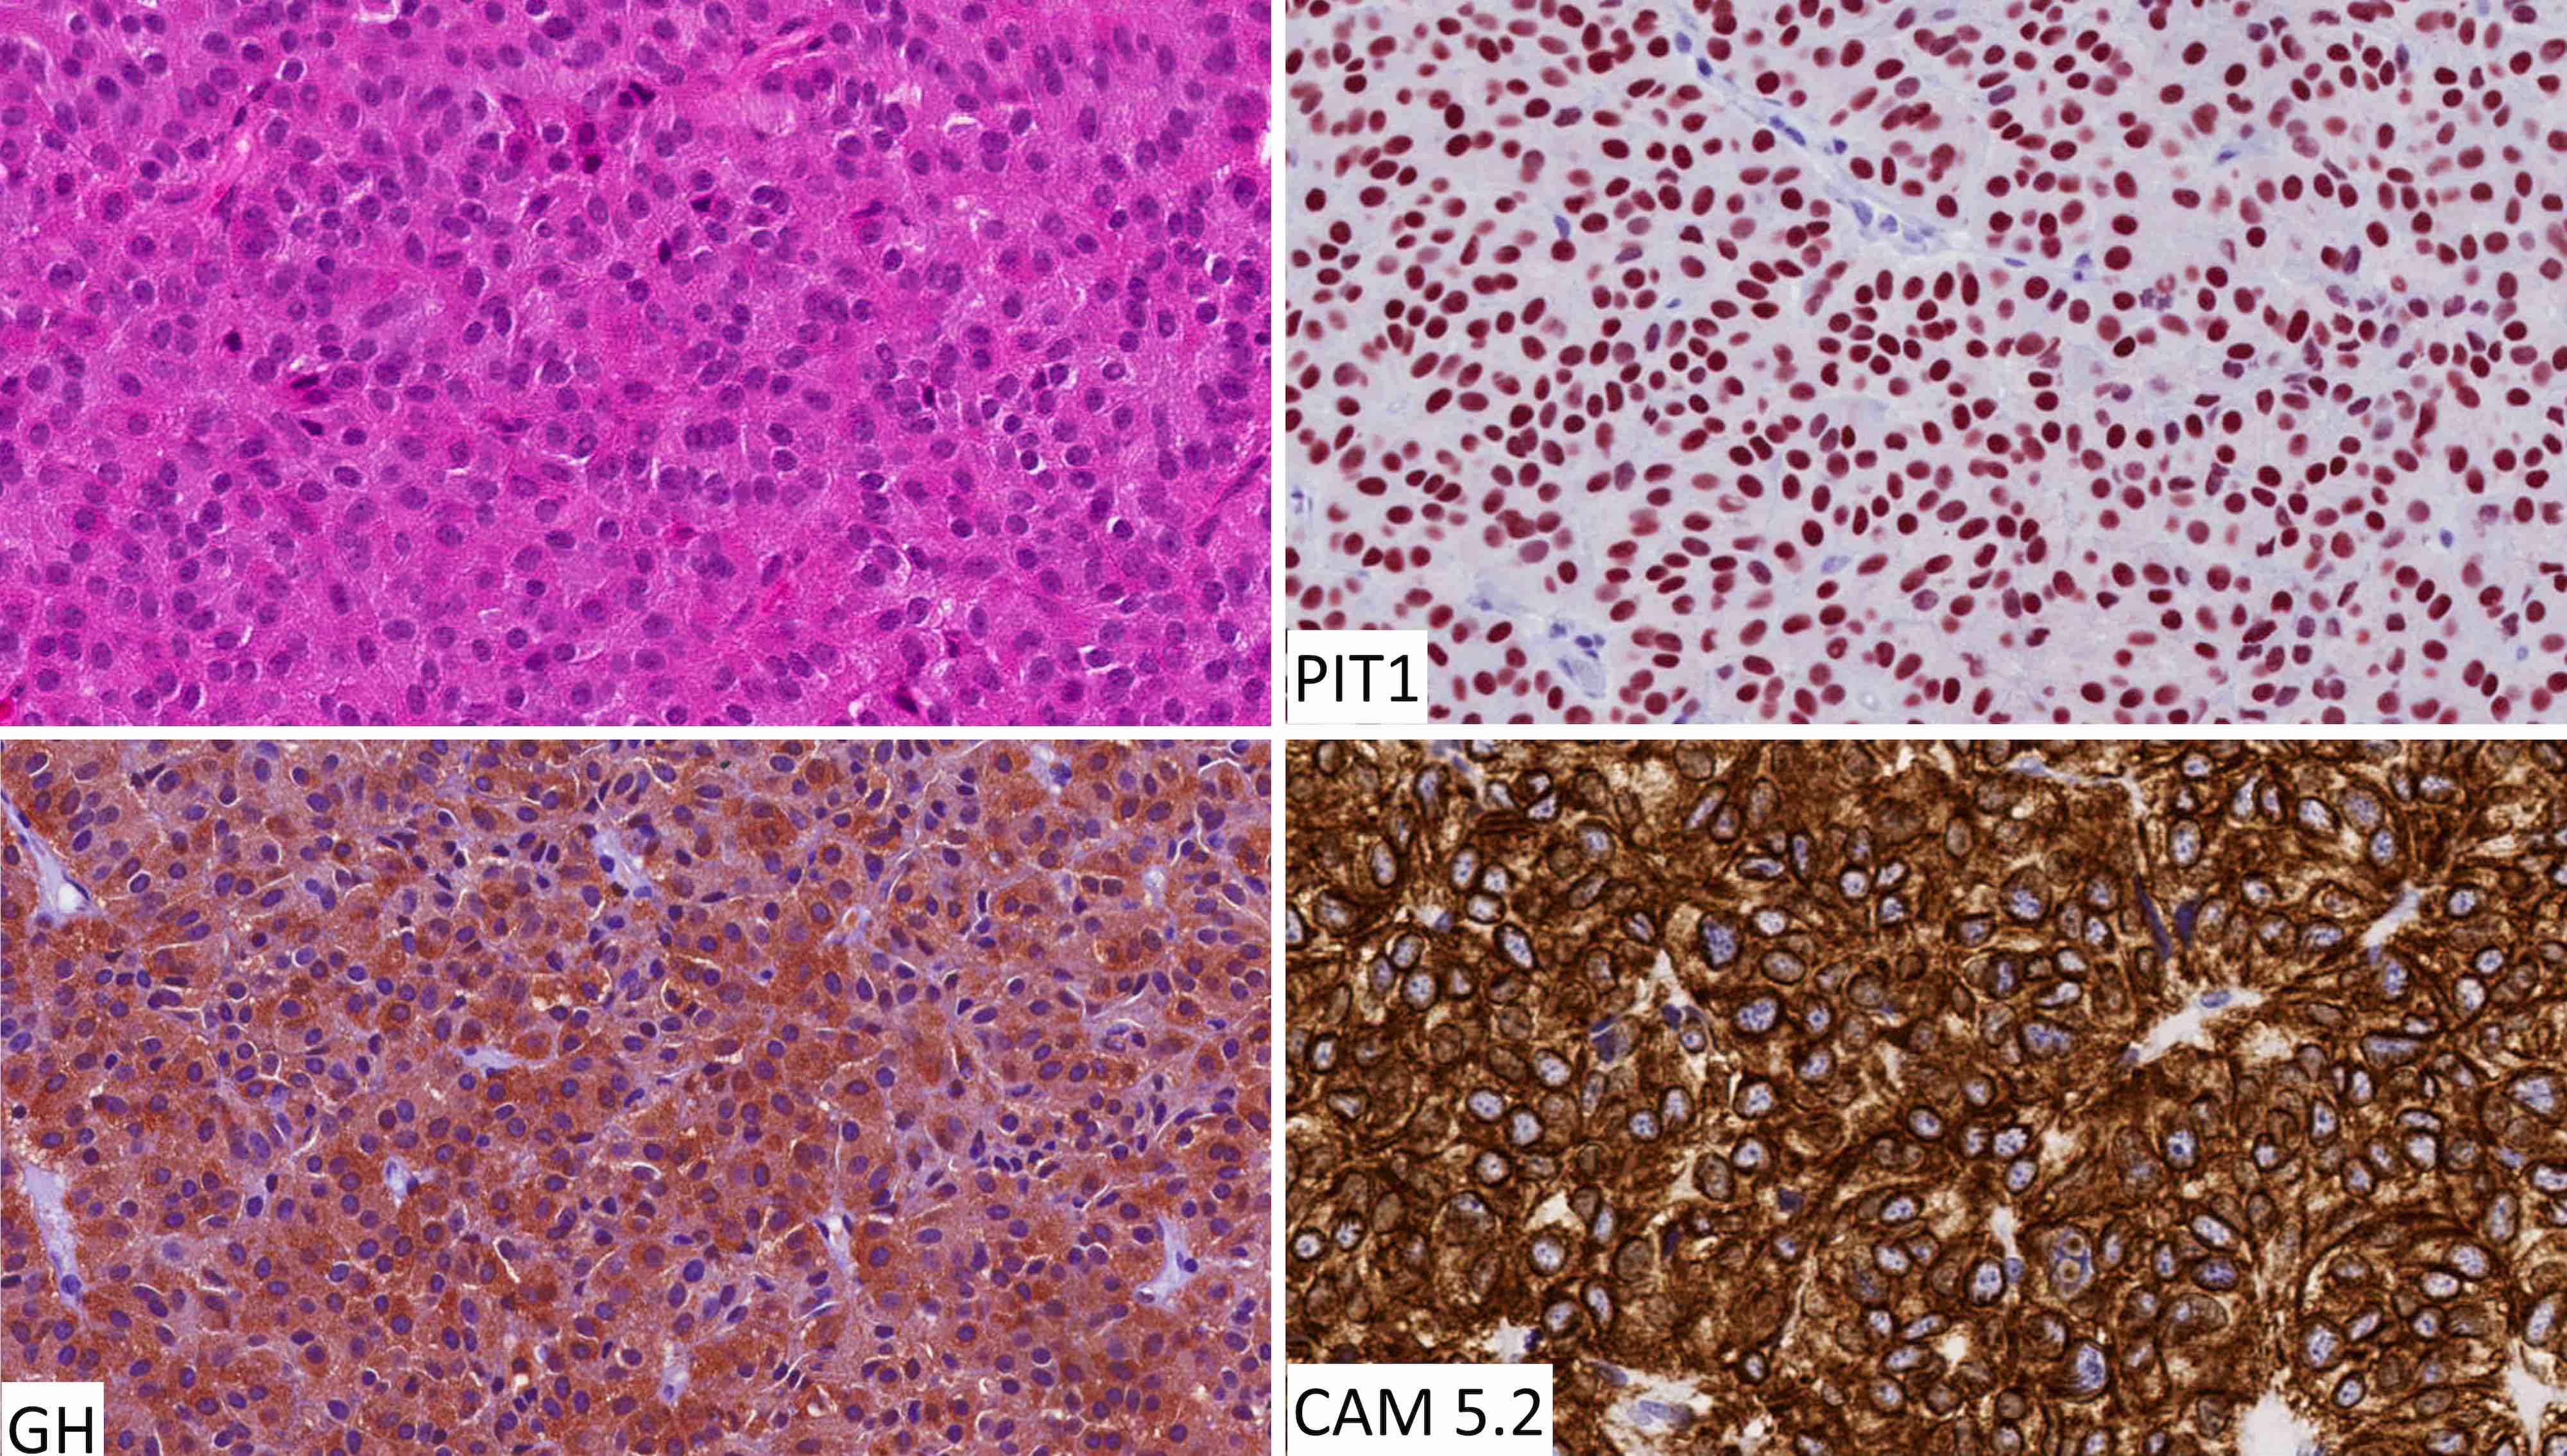

Contributed by Sylvia L. Asa, M.D., Ph.D.

Positive stains

- All pituitary neuroendocrine tumors express INSM1, synaptophysin and chromogranin; positivity for chromogranin A is variable

- Stains for pituitary transcription factors (Pit1, Tpit, SF1, ER and GATA3) and hormones provide the basis for tumor classification (see Diagrams / tables)

- Perinuclear CAM 5.2 staining pattern is a feature of densely granulated somatotroph tumors, mammosomatotroph tumors and mature plurihormonal Pit1 lineage tumors

- Paranuclear CAM 5.2 positive fibrous bodies are a conspicuous feature present in > 70% of tumor cells of sparsely granulated somatotroph tumors

- Occasional fibrous bodies can be seen in poorly differentiated Pit1 lineage tumors and acidophil stem cell tumors

- Diffuse and strong cytoplasmic CAM 5.2 staining is characteristic of corticotroph tumors

- Ring-like CAM 5.2 positivity is characteristic of Crooke cell tumors (Brain Pathol 2012;22:443)